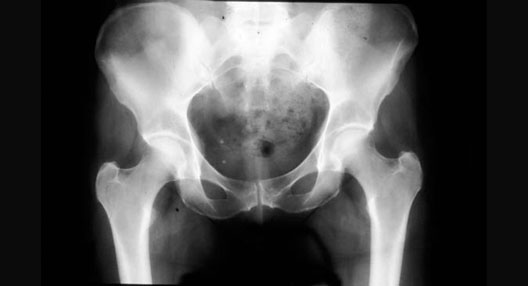

Hip X-Ray

Roll mouse over image to display labels.

1. Acetabulum

2. Pubic symphysis

3. Greater trochanter

4. Lesser trochanter

5. Anterior superior iliac spine

6. Anterior inferior iliac spine

7. Head of femur

8. Ischial tuberosity